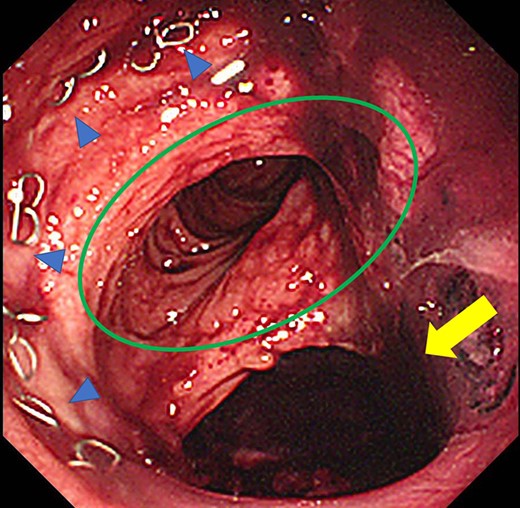

Case 1 was a 71-year-old man with a BMI of 29.7 kg/m2. Laparoscopic low anterior resection (LAR) and ileostomy was performed for rectal cancer in 2017 years. Postoperative fever and lower abdominal pain were noted, and colonoscopy was performed, and anastomotic leakage was noted with a correction of about 1/2 around the 6 o’clock direction of the anastomotic region, and fistula and formation of a large abscess cavity. After identification (Fig. 1), a tube was inserted for drainage and conservative treatment was performed. The patient was discharged on POD 46. Four months after the operation, marked improvement in the abscess cavity was noted but still remained (Fig. 2a and b). Anastomotic leakage was almost improved by colonoscopy at 17 months after surgery, but at the preference of the patient we performed colostomy 22 months after surgery (Fig. 3). It took a long time to improve intestinal movement of the colon because the large intestinal tract had not been used for a long time, and conservative treatment was performed using a nasogastric tube for paralytic ileus. Diet was initiated 7 days after surgery, and the patient was discharged from the hospital 14 days after surgery. The Wexner score [2] was 19 points one month after closure, 17 points 3 months after the operation and 16 points after 6 months after the operation, and severe anal dysfunction was observed, but gradually improved.

Colonoscopy revealed a true lumen (circle), an anastomotic site (triangle) and a cavity due to suture failure (arrow).